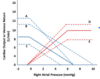

Point 0 represents LV End Diastolic Pressure (LVEDP) at baseline.

Which point best represents the LVEDP in a stiff left ventricle?

The blue line in general

A stiffer left ventricle would result in increased pressure at every volume (especially higher volumes), becuase the ventricle cannot stretch as well to accomodate volume